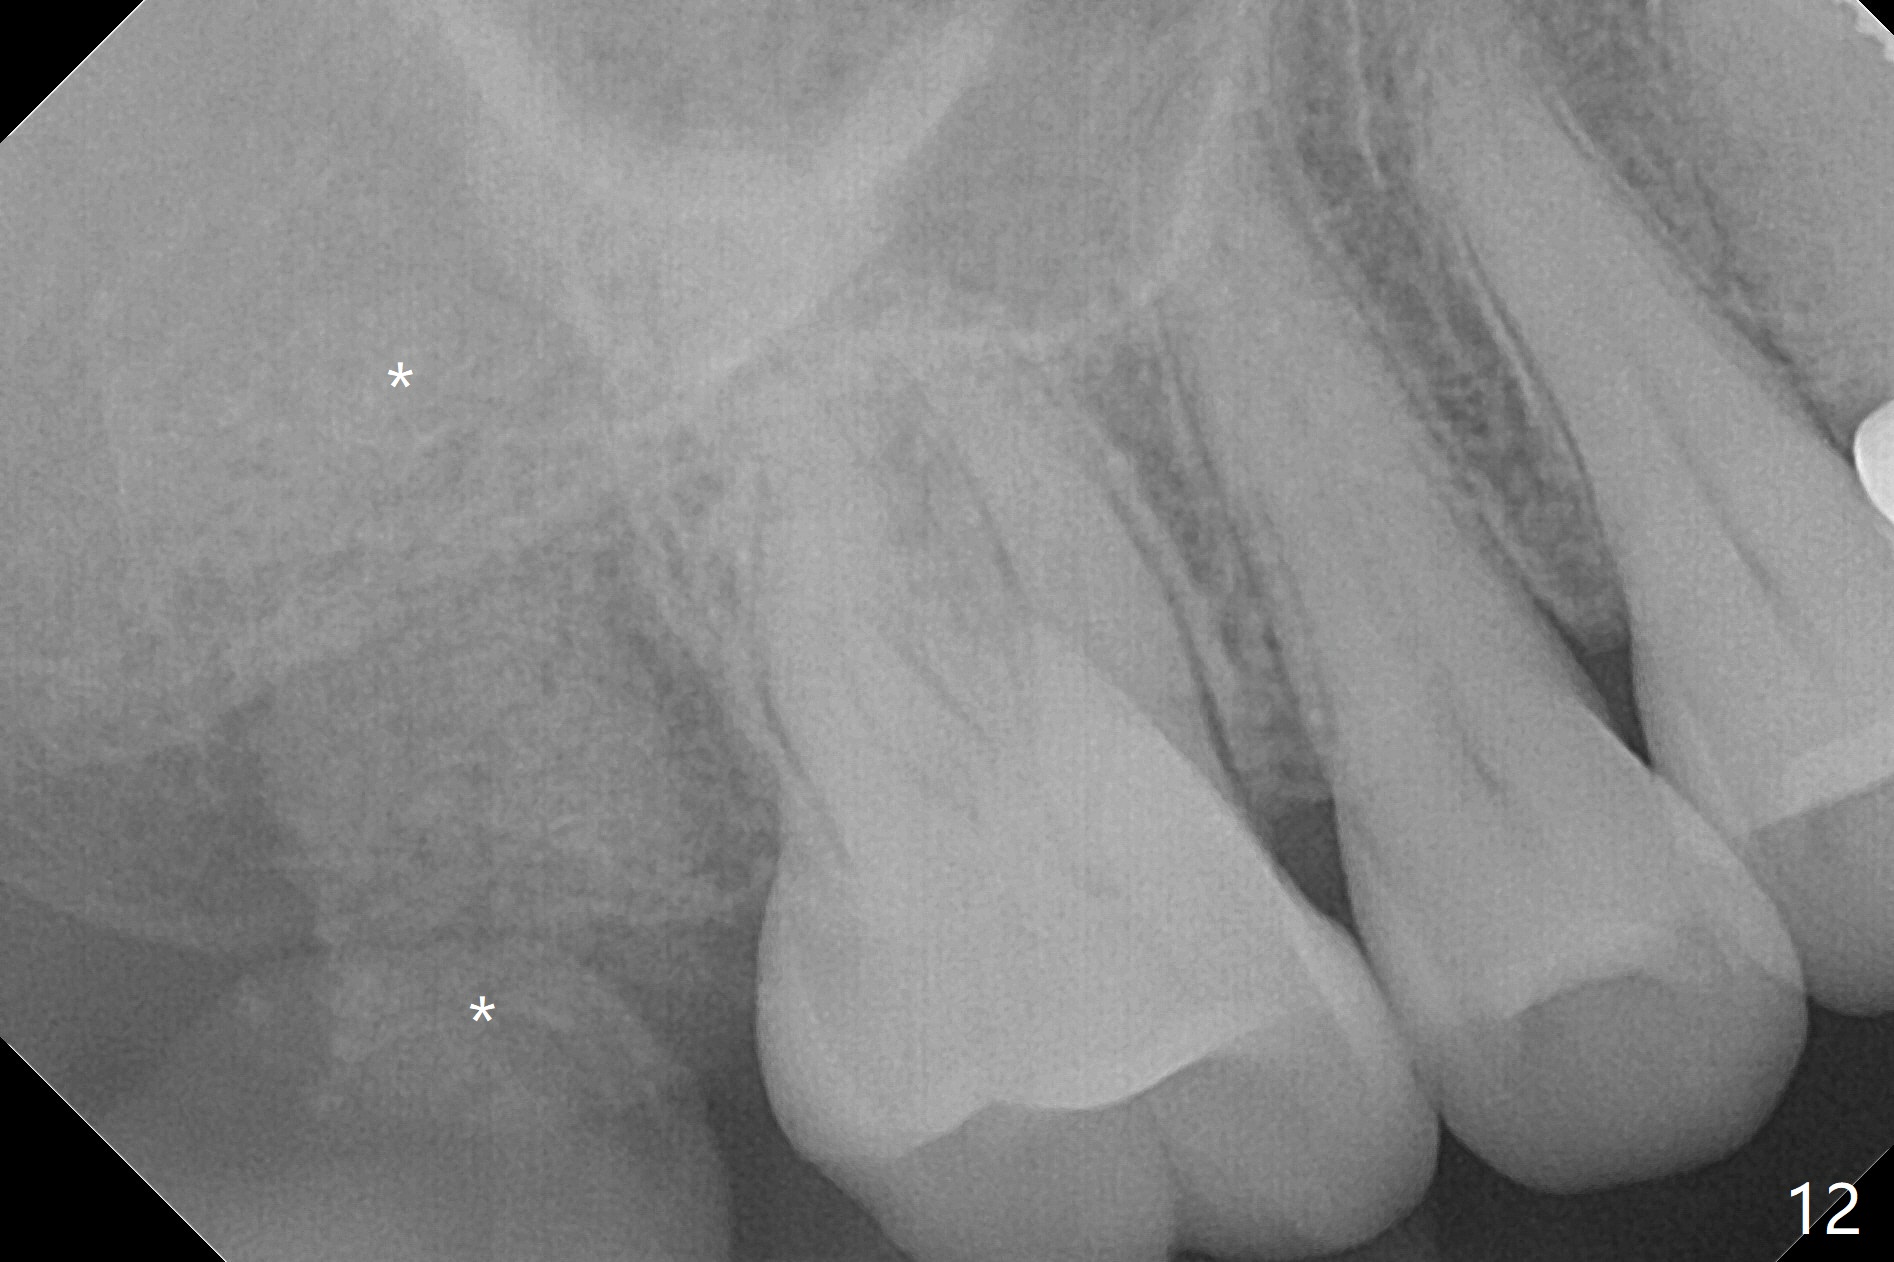

Preop exam shows that the tooth #2 has split into the buccal (Fig.1 B) and palatal (P) halves. When the tooth is extracted (Fig.2), there is a large piece of granulation tissue between these halves. The socket is large with sinus floor having pointed perforation. The latter is enlarged with rounded tapered Tatum osteotomy 2-4 mm, followed by tapered and then rounded taps. A 6.8x14 mm rounded tap has barely enough stability (Fig.3). Following placement of 2 PRF plug and 2 PRF membranes and allograft/Osteogen, a 8x17 mm cylindrical implant is placed with 60 Ncm (implant machine reading), however the implant is unstable (Fig.4). More graft is placed around the implant. With placement of 6x3 mm abutment, an immediate provisional is fabricated to close the socket. There is nasal discharge for a few days postop. PAs taken nearly 6 months postop show no bone loss (Fig.5,6). The definitive crown is cemented with access hole; there is no residual cement (Fig.7 (9 months postop)). The crown is loose 1 month post cementation (last March, Fig.8 with periimplant space (*)). The unipost was not cemented due to gag reflex. He refuses treatment immediately because of the allergy season. When he returns, spray a topical to his throat. Following crown removal, implant is found to have mobility. Panoramic X-ray (Fig.9) and CT (Fig.10,11) show fibrointegration (space) and implant intrusion into the sinus (S) without bone formation. After implant removal, the sinus floor and membrane are found to have been perforated. Osteogen plug is placed, followed by Vanilla/Osteogen (Fig.12 *) and Osteogen plug. It appears that an immediate implant is contraindicated when there is severe infection (Fig.2) with sinus floor perforation. In this case, the bone density at the upper 2nd molar is low (Fig.10 distopalatal view of 3-D image). Bone expansion and condensation is needed for implantation. Progressive loading is also necessity prior to impression.